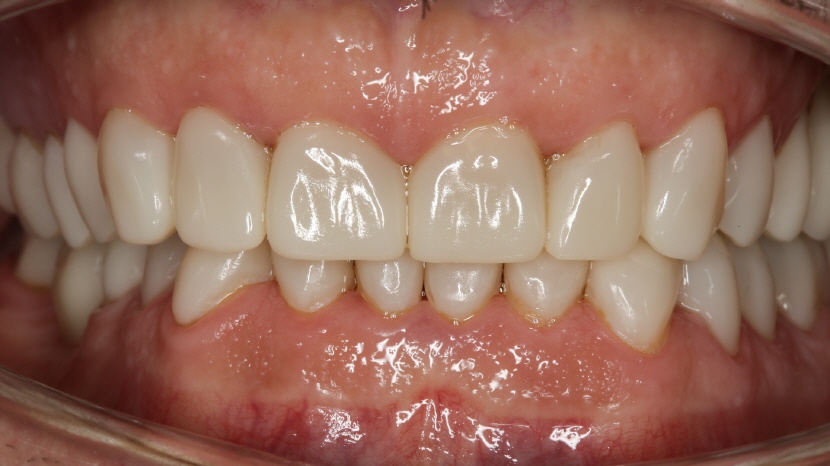

• Lippenbild nach der Gesamtsanierung mit Keramikrekonstruktionen

• Übersichtsbild nach der Sanierung

Die Zähne wurden mit Vollkeramikrekonstruktionen versorgt. Auf Wunsch des Patienten wurde die sehr helle Farbe A1 gewählt. Die Rekonstruktionen wurden direkt mit dem Cerec hergestellt. Als Keramik wurde der Lithiumdisilikat-Block der Firma GC verwendet (GC Initial LiSi A1 HT).